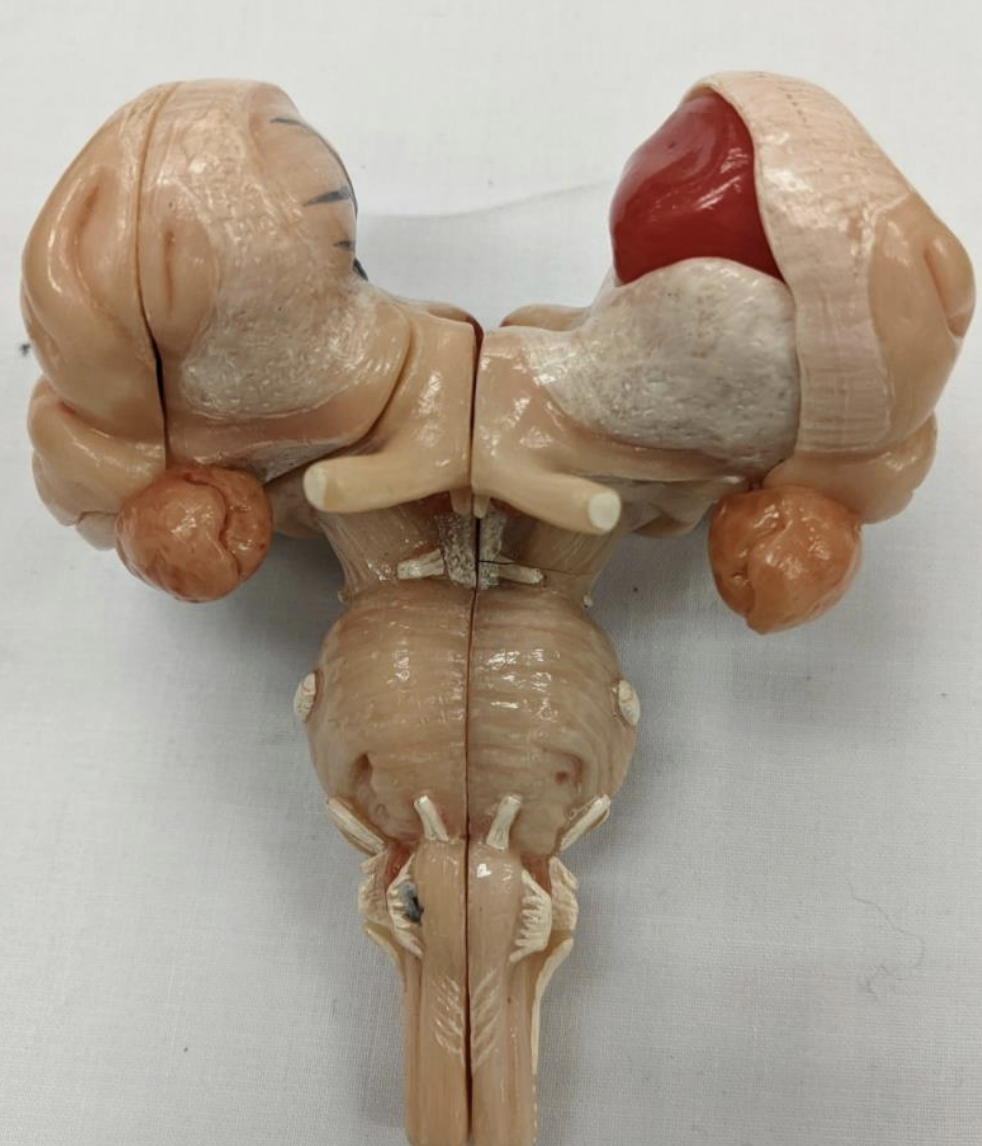

Optic chiasm

Optic chiasm

Mammillary bodies

Pathway of CNI

Cranial Nerves